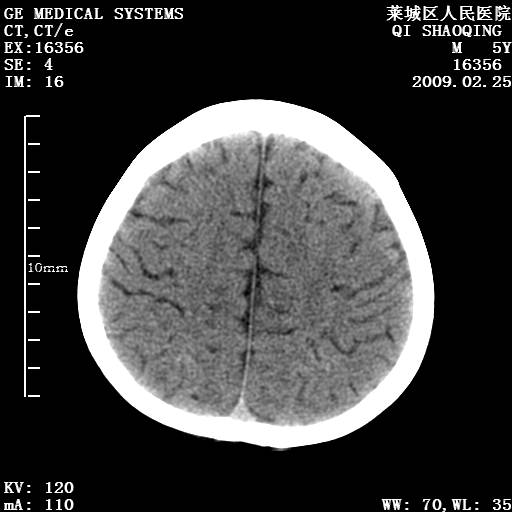

以下是引用wangzhengyuan在2009-2-28 10:22:00的发言:[br]甲状旁腺功能减退引起的脑改变.

以下是引用zsl6918在2009-2-28 10:17:00的发言:[br]首先考虑甲状旁腺功能低下所致,可结合实验室检查明确.另外需除外先天性宫内感染所致.

以下是引用余辉在2009-3-1 9:35:00的发言:[br]患者明显的肢体及智力改变,不支持fahr病,多考虑甲旁低,有可能伴有甲低(呆小症).进一步检查。